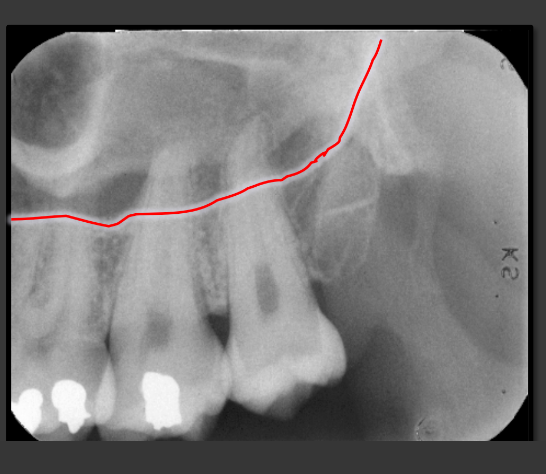

How does the external oblique ridge present in a radiograph?

Always the highest opaque line of the mandible that follows the contour of the jaw.

How does the internal oblique ridge present in a radiograph?

The second highest opaque line on the mandible that follows the contour of the jaw. Will always be below the external oblique ridge